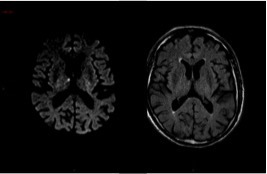

Ci-dessous des coupes axiales Diffusion et Flair de l’IRM cérébrale. La séquence T2* ne présente pas d’anomalie.

Hypersignaux diffusion à la limite de la visibilité en Flair.

L’IRM montre de multiples AVC ischémiques aigus (i. e.  6 heures), corticaux et sous-corticaux, dans des territoires artériels différents.